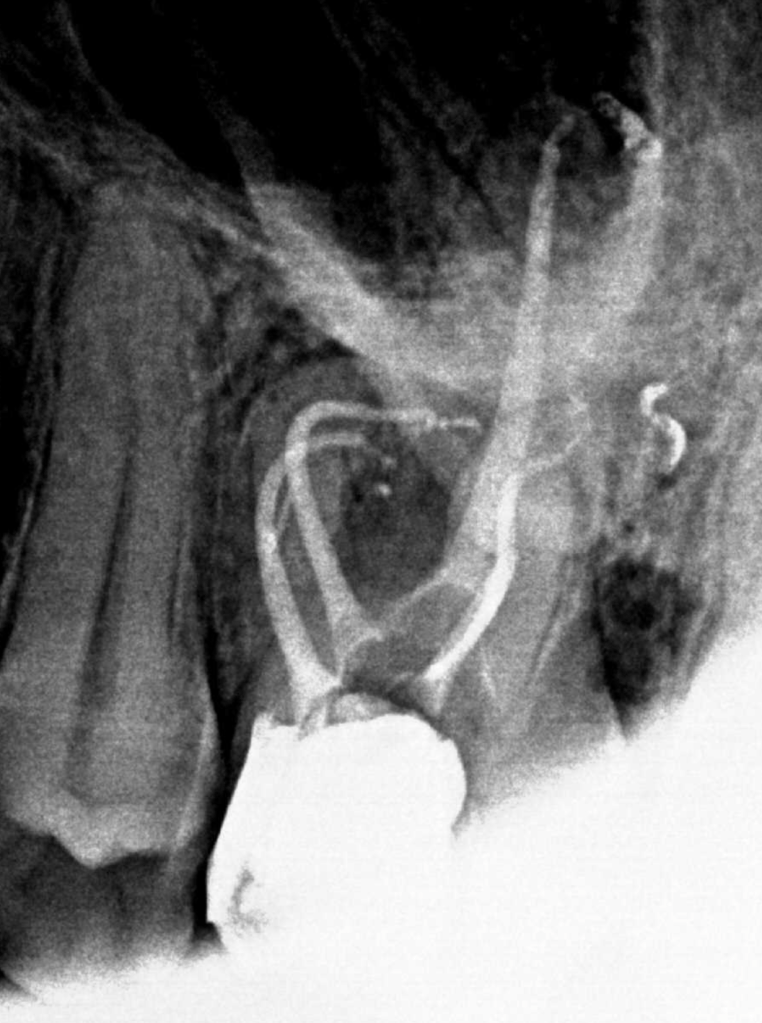

Vertical root fracture